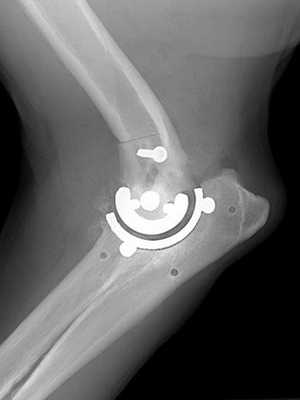

Результат операции на рентгене.

Показаниями являются фиброзный и костный анкилоз. При этом отклонении сустав частично или полностью теряет подвижность из-за патологических изменений. Причинами разрушения зачастую становятся артриты, травмы, артрозы. При множественных раздроблениях элементов, входящих в соединение, реконструкция становится невозможной. В этом случае удаляются осколки, а недостающая часть выкладывается искусственными или собственными тканями больного.

Эндопротезирование

Эта методика одна из самых сложных и в то же время эффективных. С ее помощью можно вернуть конечности былую подвижность. Суть ее заключается в замене поврежденного отдела скелета, не подлежащего восстановлению и лечению, на эндопротез, изготовленный из нейтральных материалов. Показаниями к проведению являются:

Протез вживляется через надрез на разгибательной стороне, фиксируется цементным или бесцементным способом и зашивается. Реабилитационный период составляет 2-3 месяца, но движения замещенной частью разрешаются уже через месяц после зашивания.